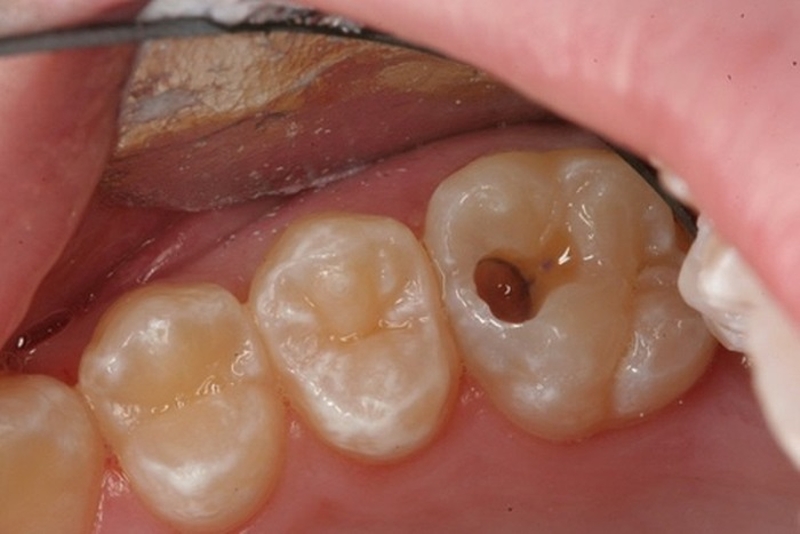

Sâu răng là tình trạng xảy ra khi tổ chức cứng của răng bị tấn công, tiêu dần đi và tạo lỗ trên mặt răng. Nếu không được điều trị kịp thời, tổ chức cứng của răng sẽ bị phá hủy nhiều hơn, ăn sâu xuống dưới và vào tủy răng dẫn đến sâu răng vào tủy. Răng bị sâu vào tủy có thể gây ra nhiều biến chứng ảnh hưởng đến sức khỏe răng miệng và toàn thân nếu không được điều trị kịp thời.

Sâu răng là tình trạng tổ chức cứng của răng bị tấn công, tiêu dần đi và tạo lỗ trên mặt răng

Khi sâu răng ăn vào tủy có thể sẽ khiến người bệnh cảm thấy đau nhức, khó chịu và ảnh hưởng đến việc ăn nhai, sinh hoạt hàng ngày. Một số dấu hiệu nhận biết như sau:

Trong hốc răng sâu thường sẽ có nhiều mảnh vụn thức ăn đọng lại kết hợp với vi khuẩn gây sâu răng tạo thành một ổ viêm. Khi tổ chức sâu răng chạm tới tủy sẽ gây viêm ở tủy răng gây đau. Tình trạng viêm có thể xảy ra ở cả buồng và tủy chân gây ra các cơn đau dữ dội.